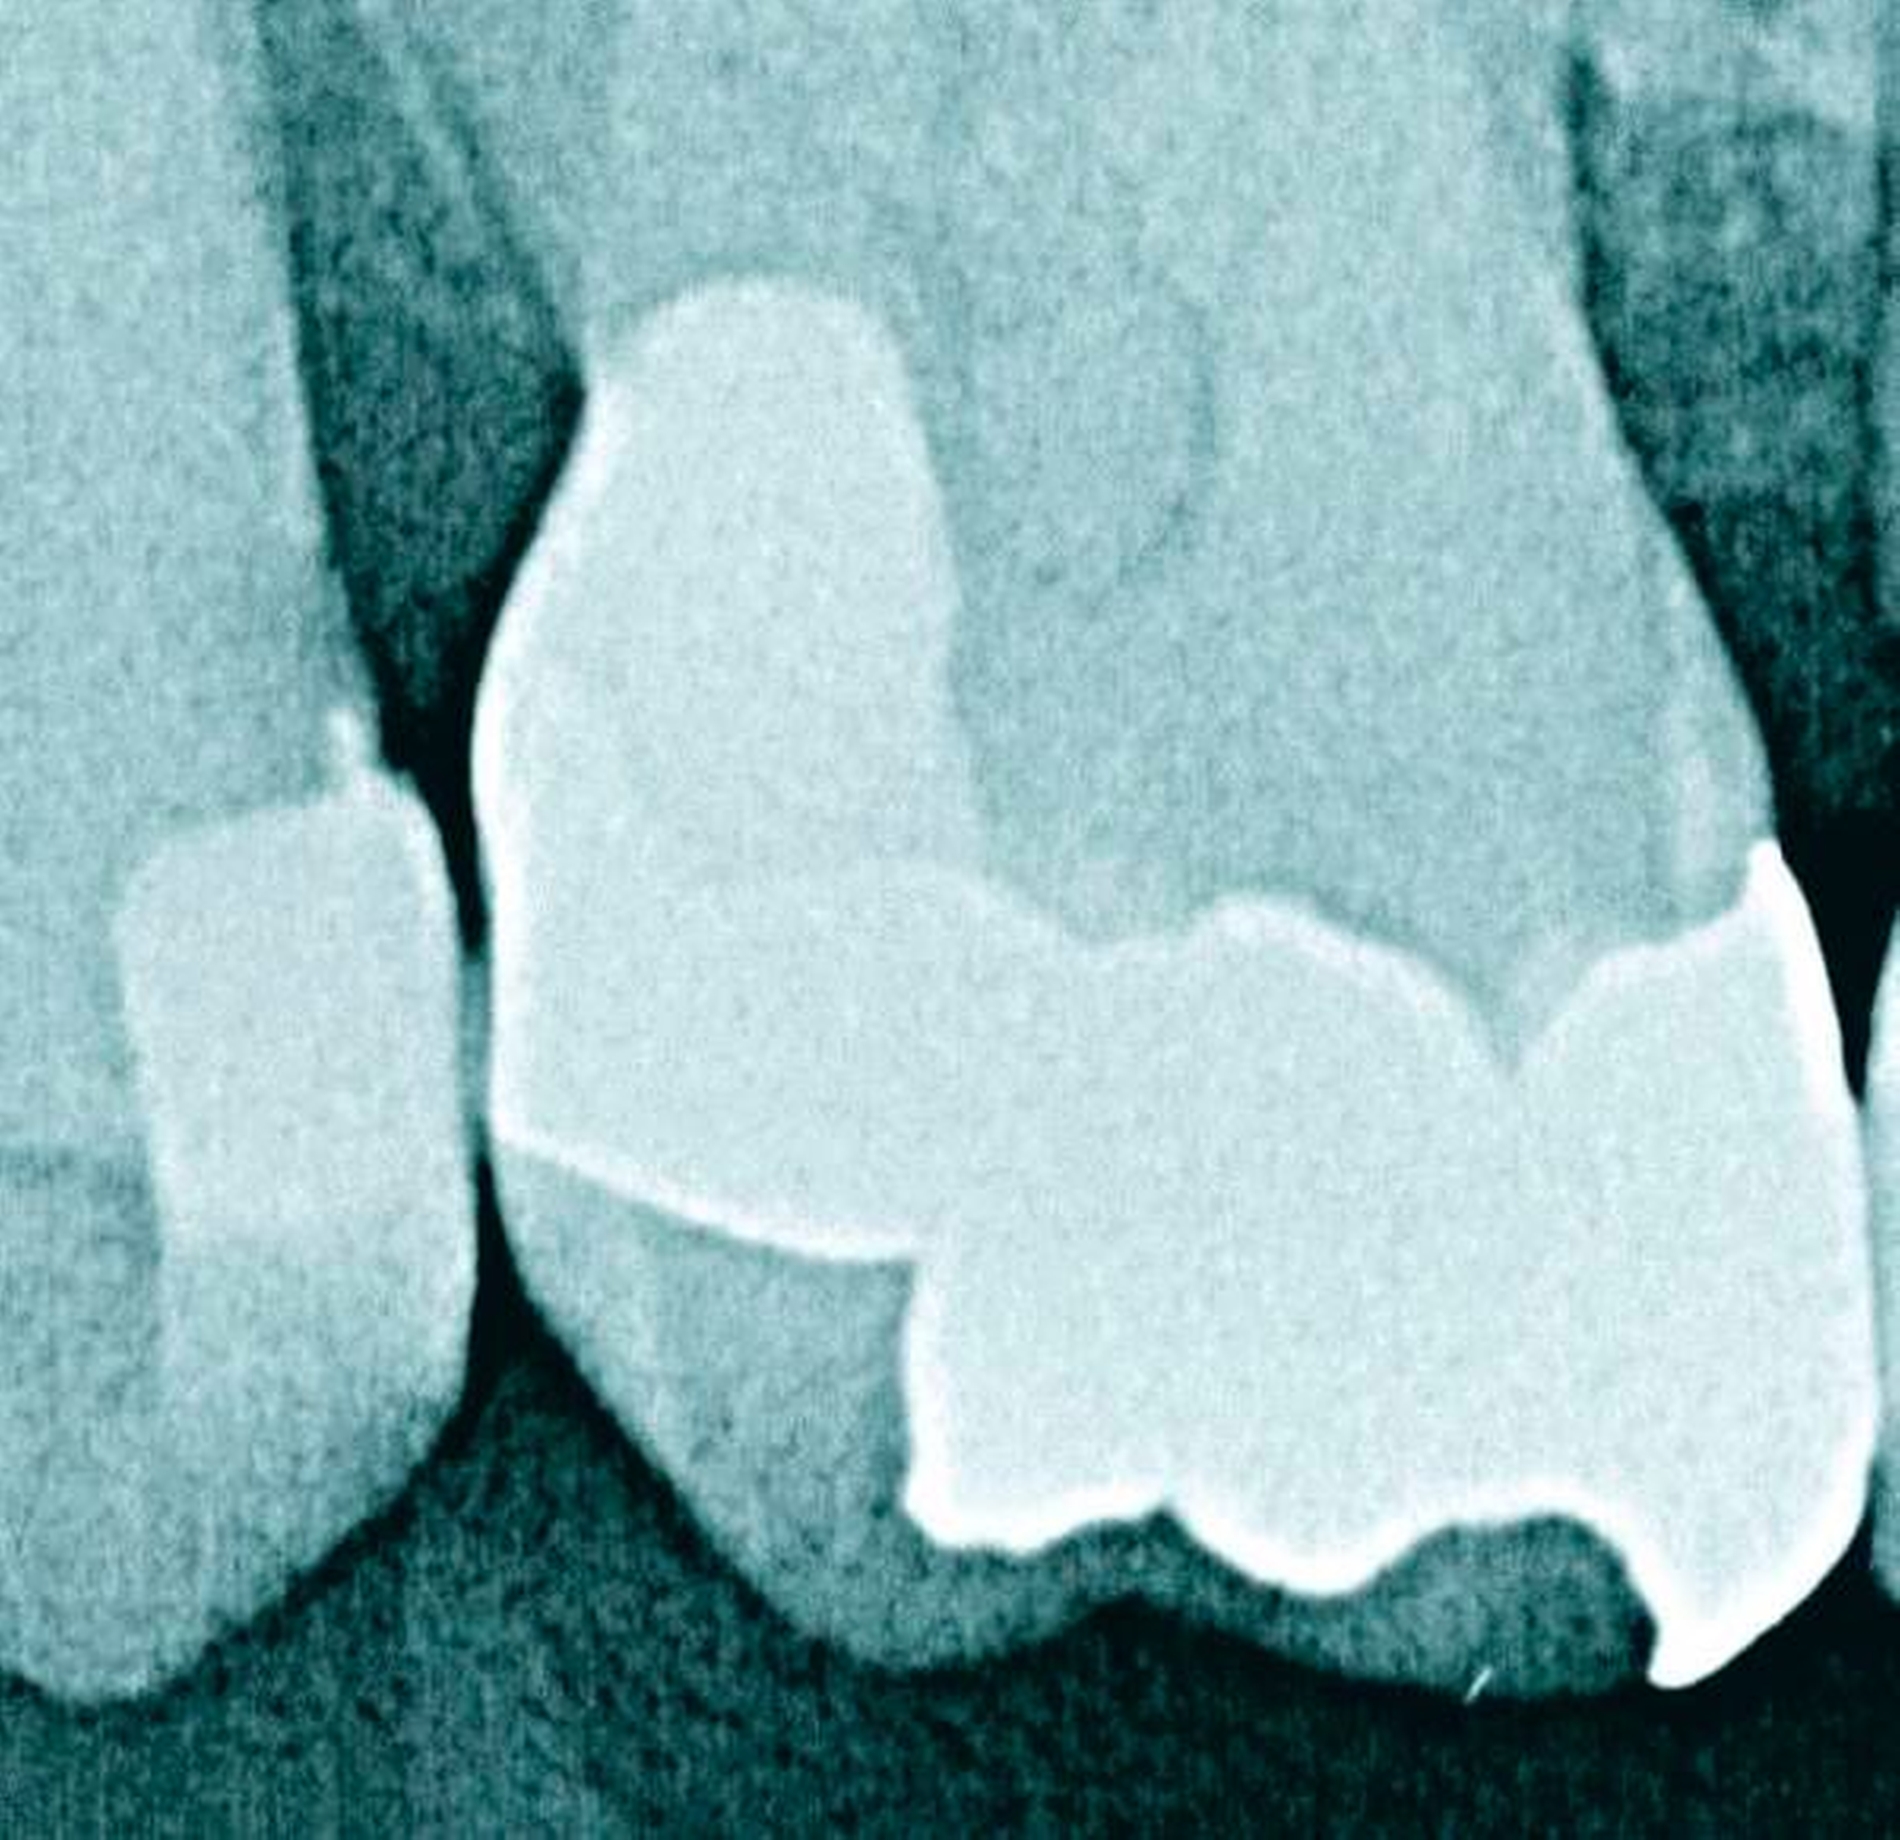

Abbildung 1a bis 1f: Direkte Überkronung im Frontzahnbereich (R1-Technik)

In den Abbildungen 1 bis 3 werden Optionen für frugale Interventionen auf restaurativem Sektor aufgeführt. Es handelt sich um direkte Vollüberkronungen im Frontzahnbereich (hier: hergestellt in R1-Technik / einphasig) (Abbildung 1), direkte Teilüberkronungen im Seitenzahnbereich (hier: hergestellt in R1-Technik / einphasig) (Abbildung 2), Reparatur-Restaurationen im Seitenzahnbereich (hier: hergestellt in R2-Technik / zweiphasig) (Abbildung 3). Technische Einzelheiten zur Vorgehensweise und den Ergebnissen sind an anderer Stelle beschrieben (Literatur siehe oben).

Am Beispiel von Abbildung 1 (stark zerstörte Zahnkrone eines Schneidezahns) kann das Prinzip der frugalen Intervention erläutert werden:

Früher wurde für die hier beschriebene Ausgangssituation folgendes Procedere gewählt:

Wurzelkanalbehandlung des vitalen Zahns als Voraussetzung für eine Stiftversorgung

Einsetzen eines Wurzelkanalstifts

Einsetzen einer indirekt gefertigten Stiftkrone

Durch die Erfolge der Adhäsiv- und Komposittechnik kann heute folgendermaßen vorgegangen werden:

Verzicht auf Wurzelkanalbehandlung / Erhaltung der Vitalität des Zahns

Verzicht auf Wurzelkanalstift

direkte minimalinvasive Kompositkrone (Verzicht auf indirekte Vorgehensweise)

Die potenziellen medizinischen und ökonomischen Vorteile dieser frugalen Intervention sind vielfältig:

Schonend: Die oralen Strukturen werden geschont und die Versorgung ist hinreichend stabil. Durch den Verzicht auf Wurzelkanalstifte wird das Wurzelfrakturrisiko reduziert. Zudem können Material-, Geräte- und Personalressourcen aus Praxis und Techniklabor, die beim klassischen Vorgehen anfielen, reduziert werden.

Bezahlbar: Hier ist anzumerken, dass die Kosten unter anderem von der zahnärztlichen Expertise abhängig sind: Zahnärzte, die mit direkten Restaurationen große Erfahrung haben, können zügiger und mit besserem Erfolg arbeiten als Kollegen mit geringerer Erfahrung auf diesem Gebiet; die Behandlung ist gleichwohl anspruchsvoll und deshalb nicht „billig“. Eine direkte Vorgehensweise kann, muss aber nicht automatisch zeit- und kostensparender sein als eine Versorgung mit indirekt hergestellten Werkstücken.

Gut genug: Ästhetische Feinheiten lassen sich bei direkten Restaurationen nicht immer in gleicher Perfektion einarbeiten wie bei indirekt gefertigten Kronen, auch die Stabilität des Hochglanzes lässt bei einigen Kompositpräparaten noch zu wünschen übrig. Andererseits erlauben die direkten Verfahren inzwischen mitunter sehr flexible Vorgehensweisen, die sich auch mit Farb- und Formkorrekturen von Zähnen kombinieren lassen. Die Erwartungen eines großen Teils der Patienten werden hinreichend erfüllt und die Nutzen-Risiko-Relationen wie auch die Aufwand-Kosten-Relationen erscheinen – wenn auch nicht durchgängig – so doch zumindest in vielen Fällen günstig.